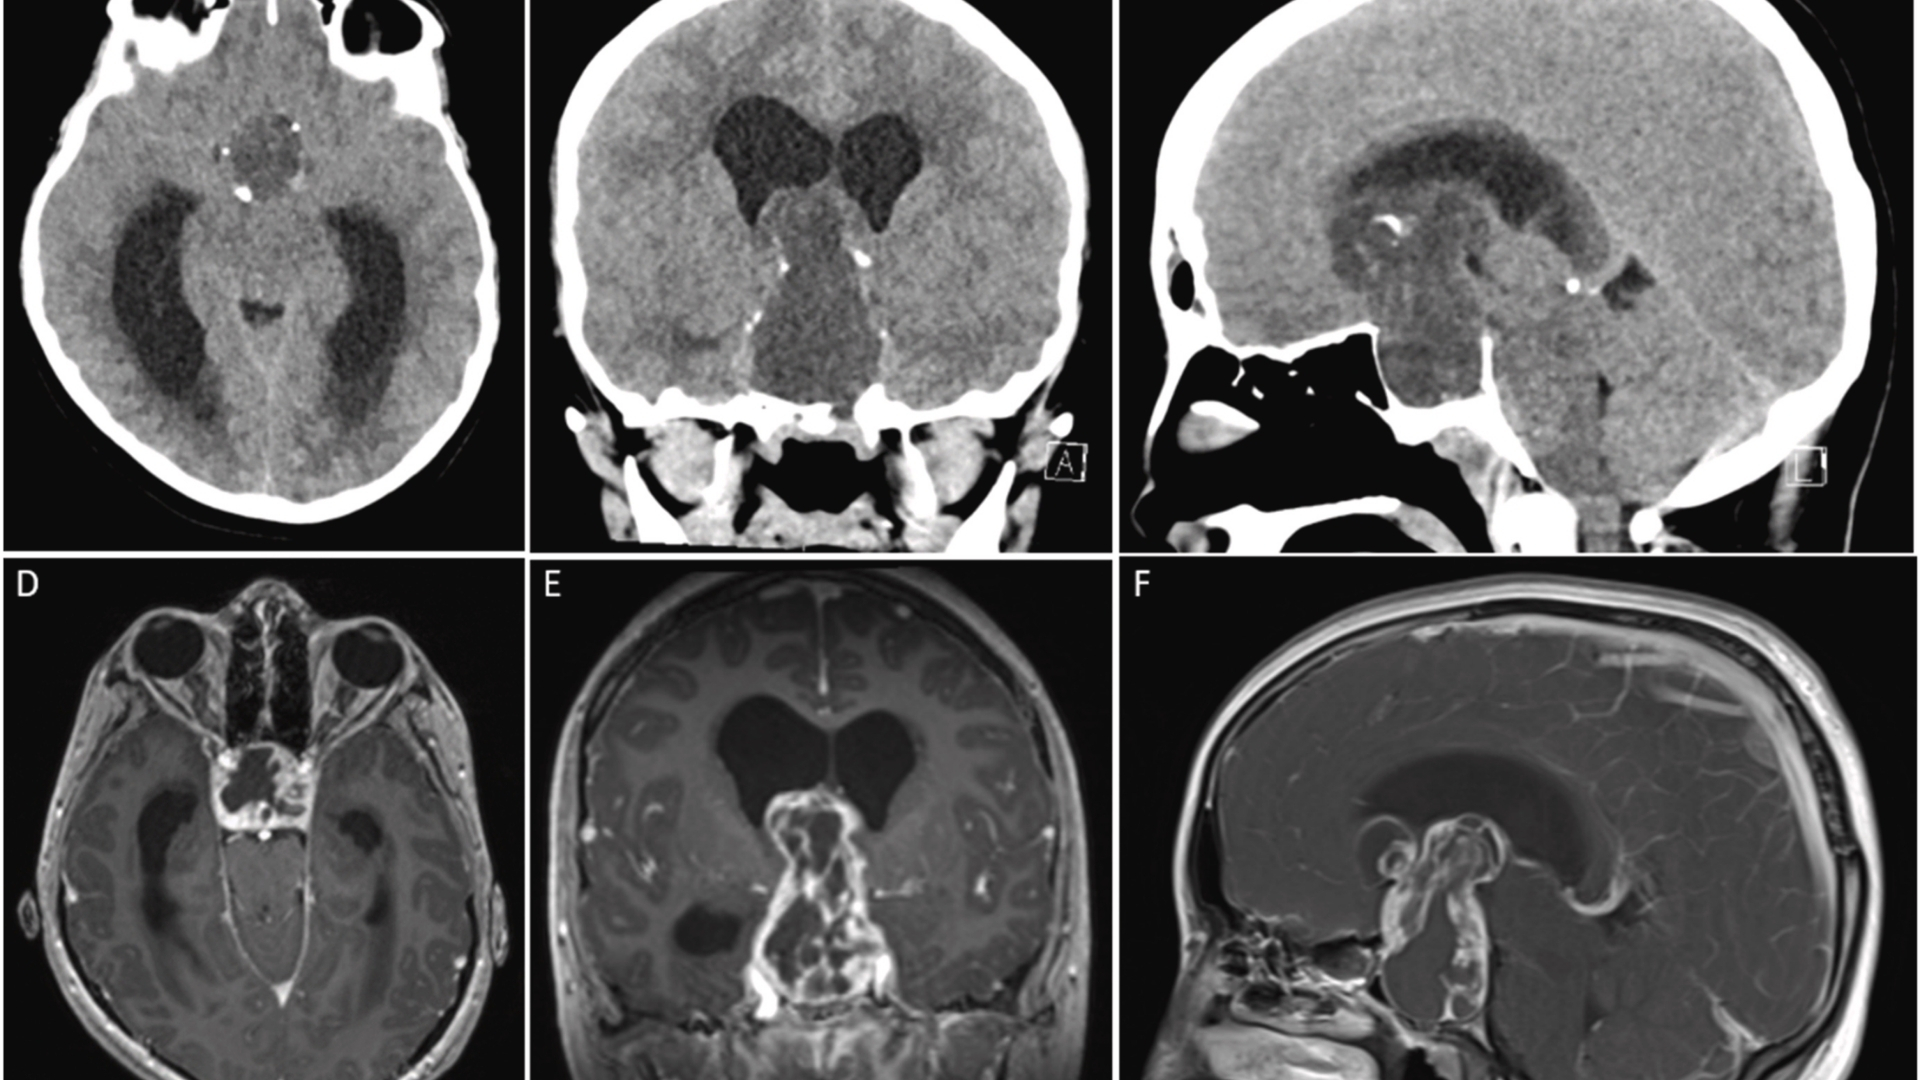

了解顱咽管瘤的生物學特性至關重要。這些腫瘤來自於 Rathke「s pouch 的殘餘物,Rathke」s pouch 是一種胚胎結構,對腦下垂體的發育非常重要。這些腫瘤常呈現囊狀及鈣化外觀,可透過影像技術 (如 MRI 或 CT 掃描) 看到。

採用先進的 MRI 和 CT 成像技術進行早期診斷評估,對於減輕腫瘤相關的損害和提高治療成功率仍然至關重要。定期的醫療篩檢,尤其是針對易受影響的年齡層,可顯著改善治療效果、及時介入治療,並減少長期後遺症。在全港鼓勵公眾認知運動,對於減少診斷延誤和提高生活品質仍是不可或缺的。